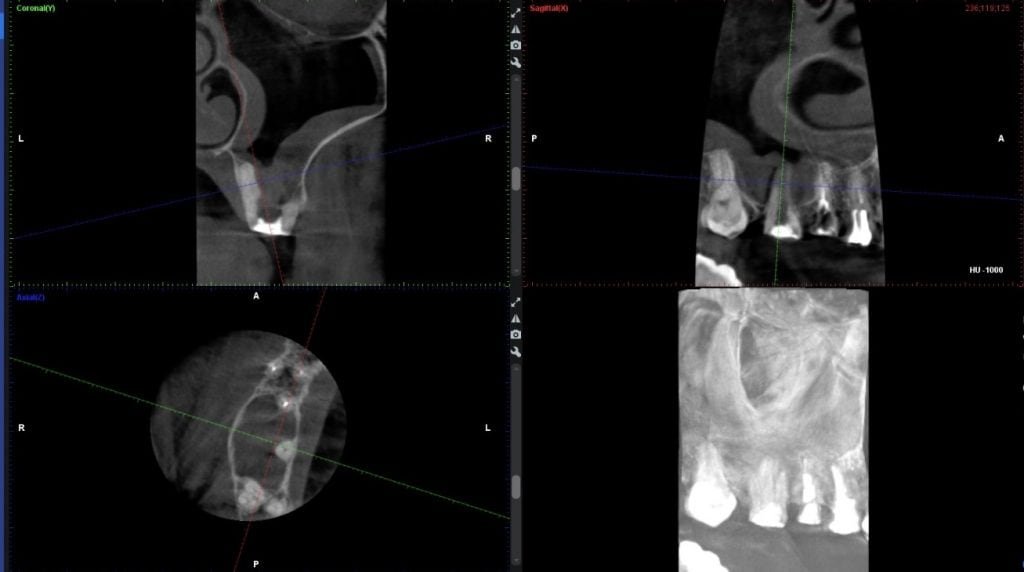

Caz 4 – Molar superior cu rădăcini în sinusul maxilar

Un molar superior cu rădăcini în sinusul maxilar a fost perforat accidental de catre alt medic în timpul primei intervenții (fără microscop), creând o comunicare directă cu sinusul. În endodonția convențională, acest caz ar fi fost considerat netratabil, întrucât lucrul cu hipoclorit de sodiu în sinus este imposibil. Alternativa clasică ar fi fost extracția, sinus lift-ul și implantul – o procedură complexă și de durată.

In clinica noastra, laserul a permis salvarea dintelui, deoarece s-a lucrat doar cu apă și lumină, fără substanțe iritante pentru sinus. Perforația a fost închisă cu un ciment biocompatibil și bactericid, iar dintele a fost restaurat protetic. La CT-ul de control la 9 luni, sinusul maxilar apare complet curat și vindecat.